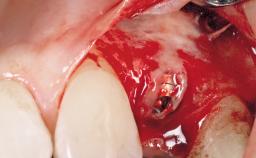

Late Placement of an Implant in a Maxillary Left Central Incisor Site

Type of Implants Two-Piece

Attachment Two-Piece

Abutment Type Customized